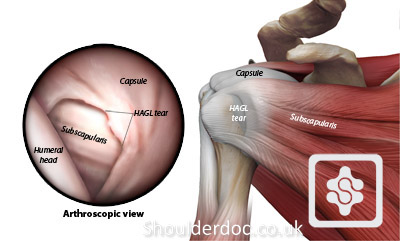

Glenohumeral ligament: анатомия и функции плечевого сустава